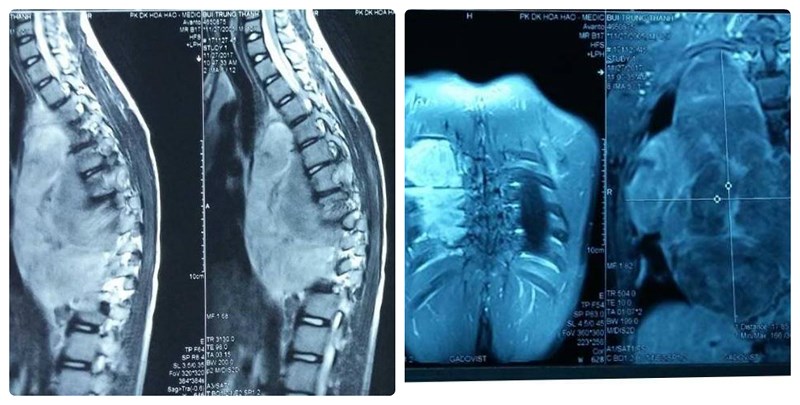

Theo Phó GĐ BV nhi đồng 1 Đào Trung Hiếu, khi chụp X-quang và MRI phát hiện cột sống bệnh nhi bị vẹo và có khối u lớn với đường kính 21 cm chèn ép phổi, tim, động mạch chủ.

Một phần của khuối u cũng chèn ép vào tuỷ, làm cho bé liệt chân, rối loạn tiêu, tiểu.

Phim chụp X-Quang cho thấy khối bướu khủng trong lồng ngực lan sang ống sống gây biến dạng cột sống. |